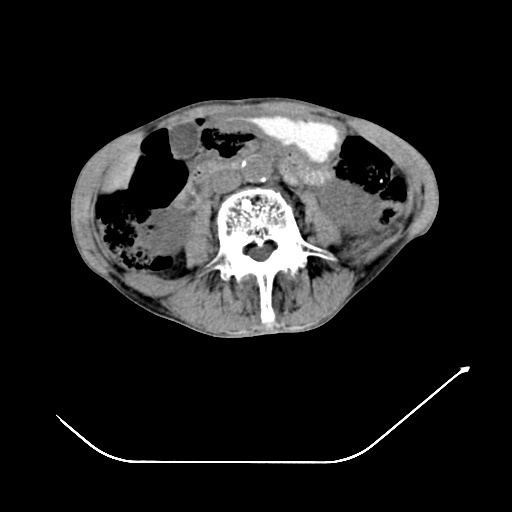

以下是引用zsl6918在2008-8-25 21:55:00的发言:[br]符合右肺周围性肺癌并肺内转移,左肺结核球。双肺肺气肿。腰椎附件转移。

以下是引用随光逐影在2008-8-25 22:03:00的发言:[br]1)考虑右肺下叶周围性肺癌并肺内转移,腰椎附件转移。2)左上肺结核(结核球形成)。3)双肺肺气肿(多发肺大泡形成)。4)双肺门区及纵隔内多发淋巴结钙化。